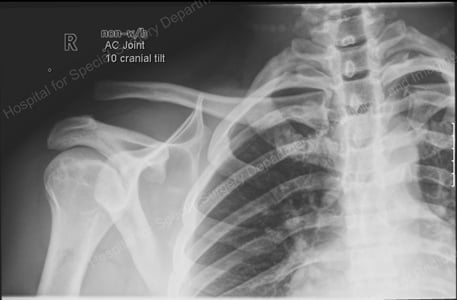

X-ray image of a shoulder separation